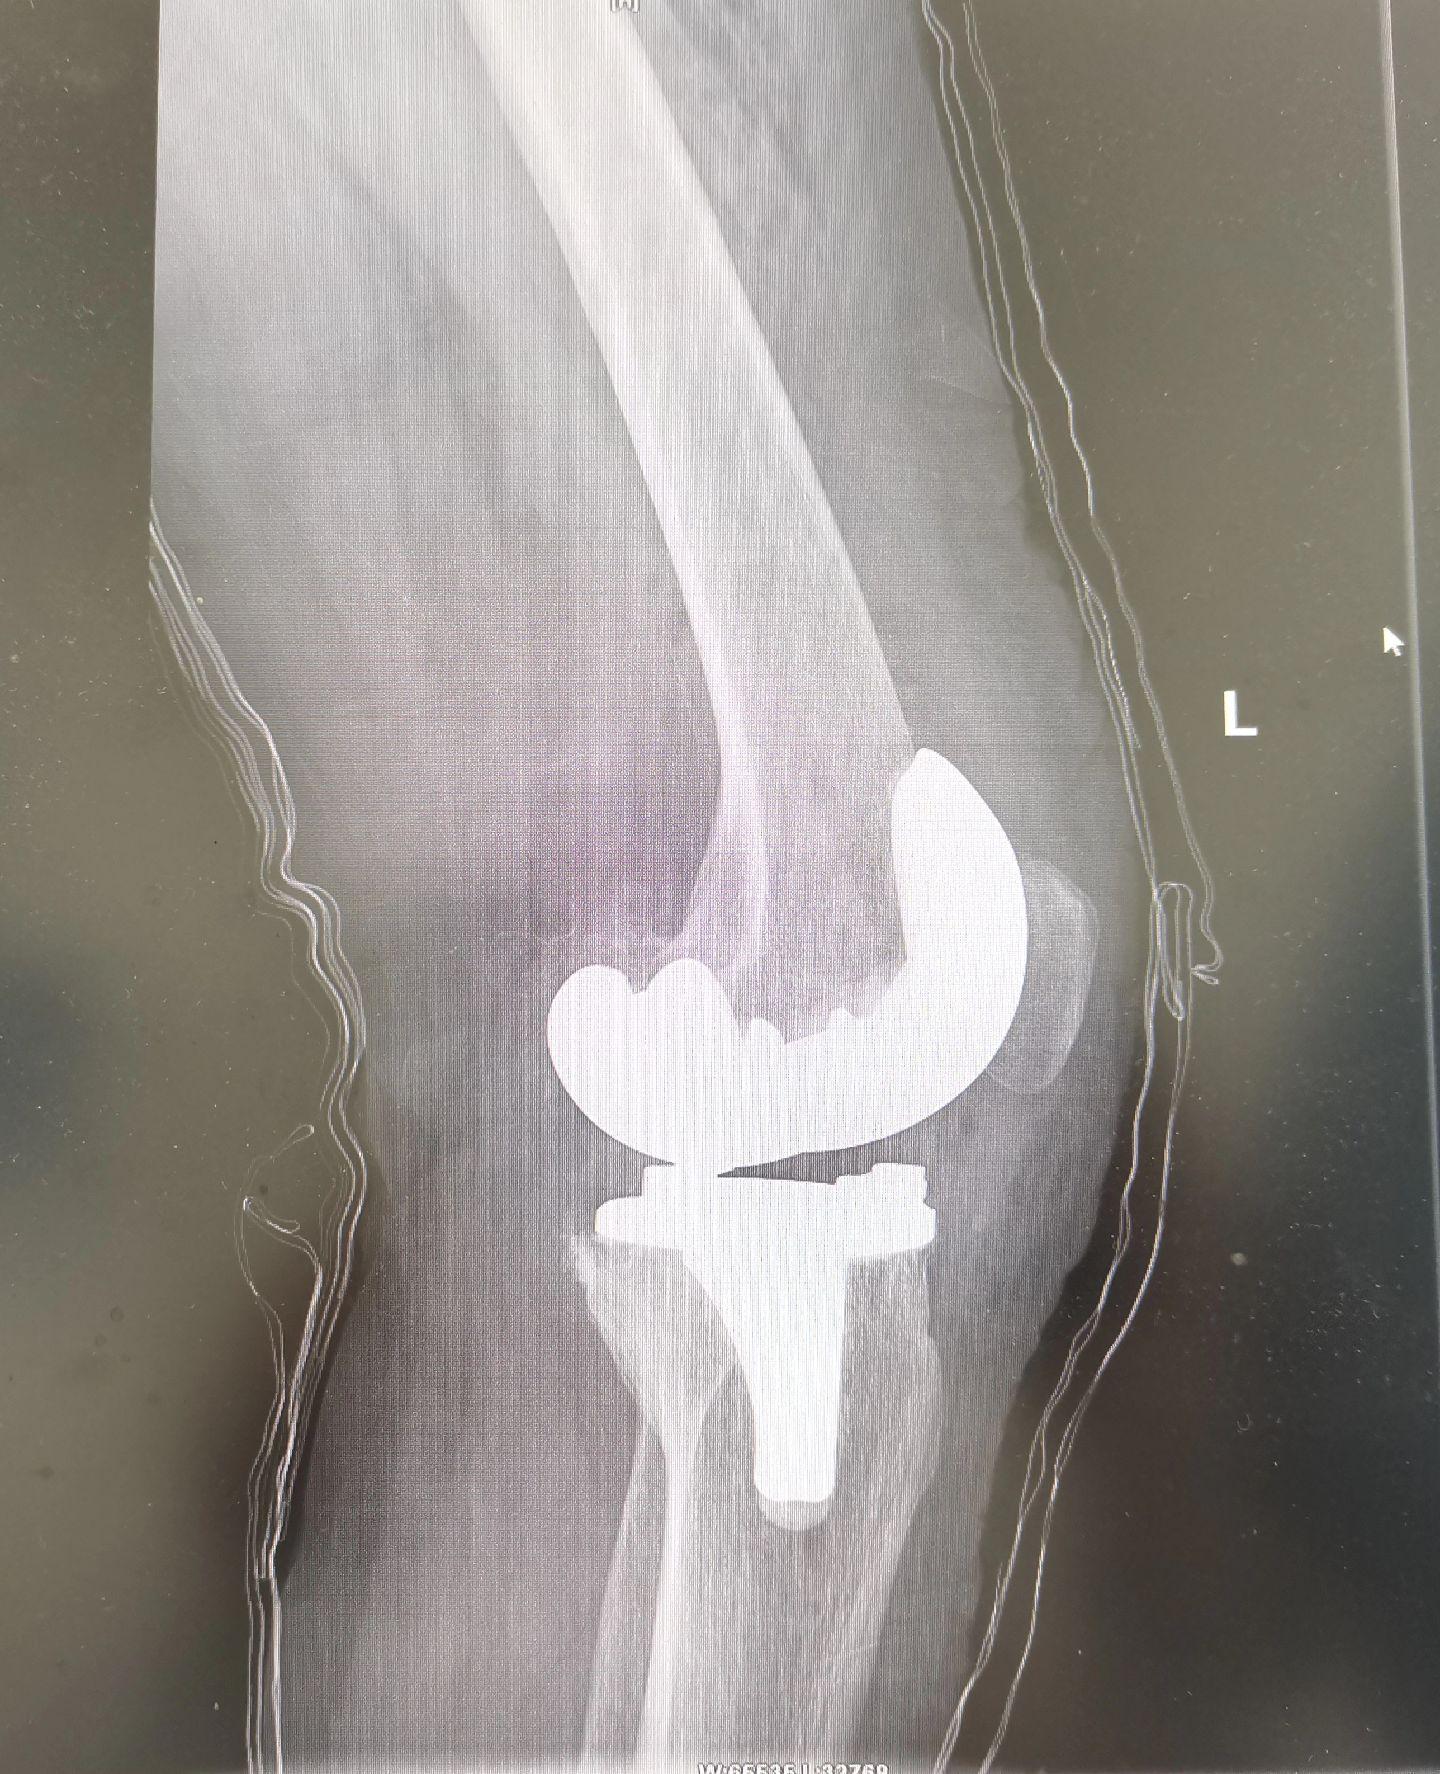

膝关节置换TKA.骨关节炎重度内翻合并屈曲挛缩畸形,无法行走,一期行双侧TKA,愿每一位患者都能得到有效的治疗,都能早日恢复正常生活🌹